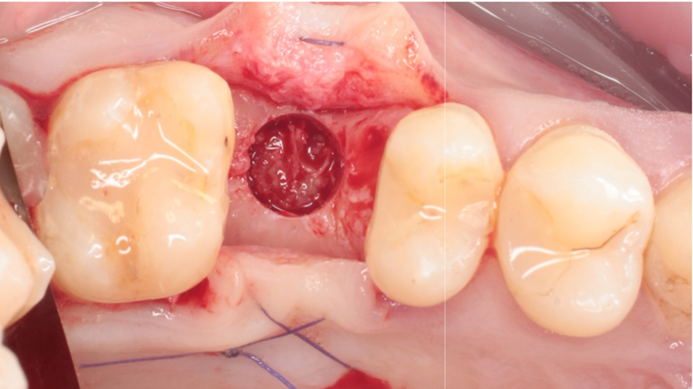

Clinical case: # 46 implant placement & GBR using i-Gen membrane for significant vertical resorption & mixed bone defect

- Courtesy of Dr. Iulian Filipov, Romania -

AnyRidge, mandibular posterior, i-Gen, resorption, bone defect, bone regeneration, space management, #46, GBR, Dr. Iulian Filipov

AnyRidge implant system, i-Gen